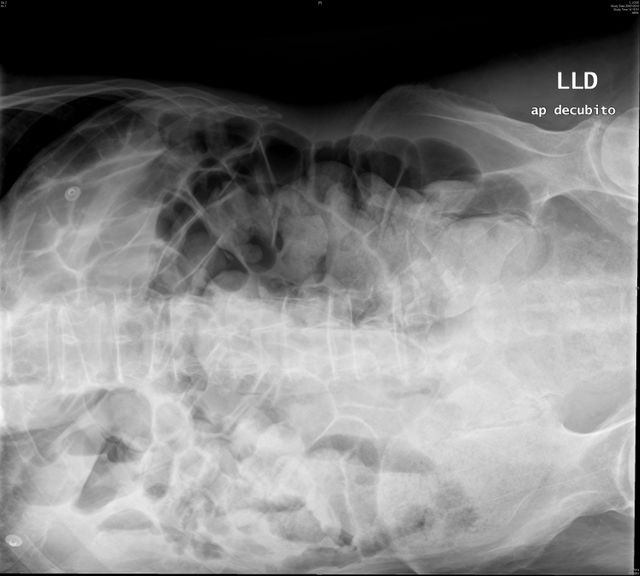

Diverticulosis de colon. Megacolon.

Dolico-megacolon.